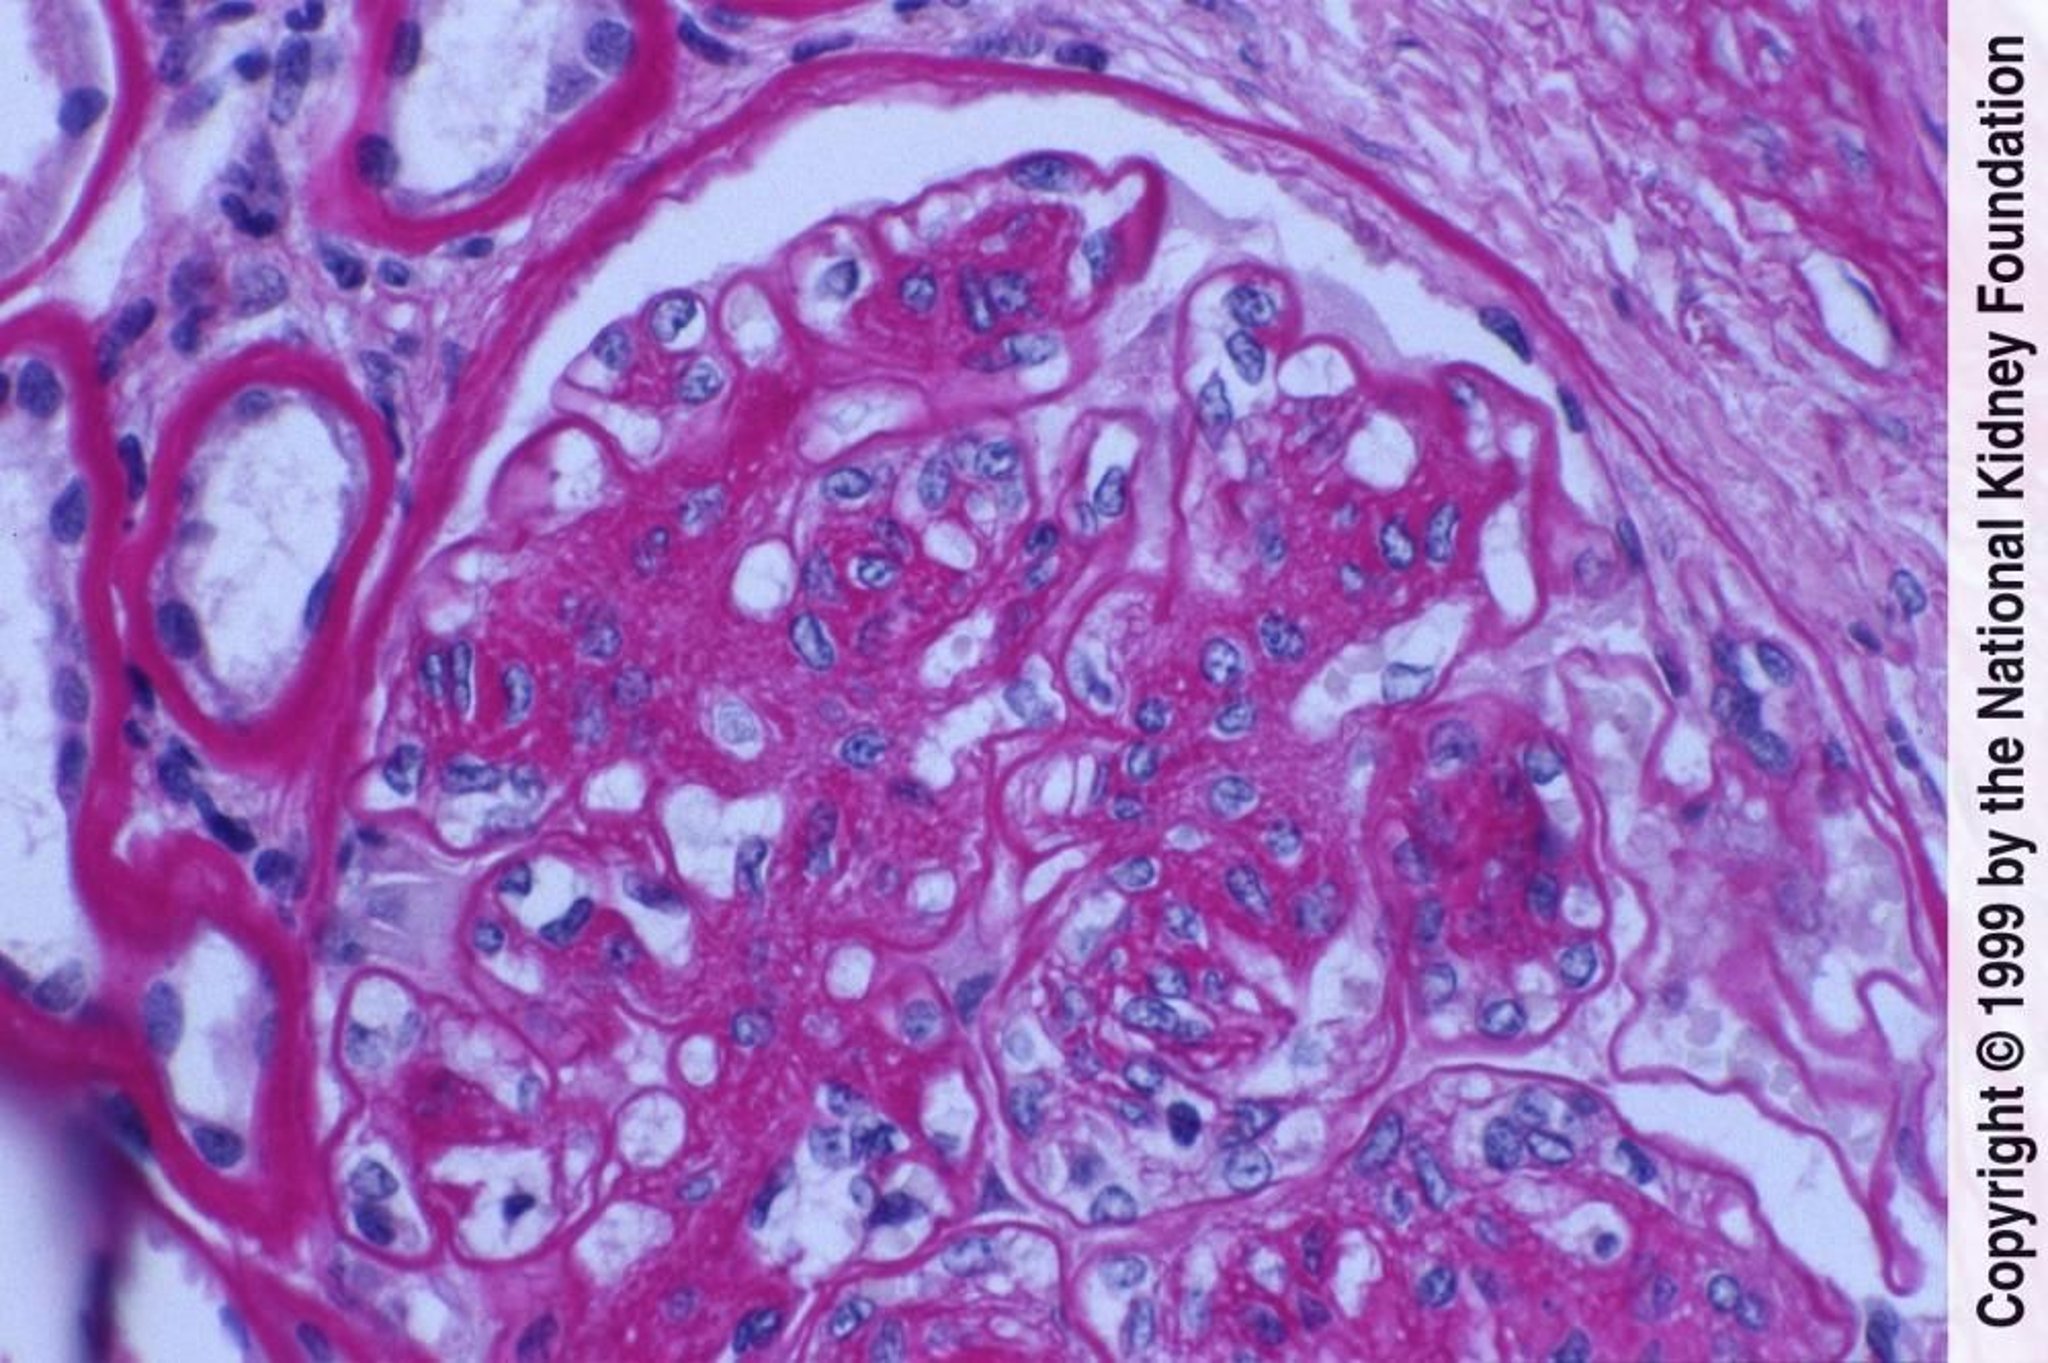

Nefropatia diabetica (proliferazione delle cellule mesangiali ed espansione della matrice)

La proliferazione delle cellule mesangiali e l'espansione della matrice con danno endoteliale si manifestano qui come ispessimento delle membrane basali glomerulari senza evidenti depositi di immunocomplessi (colorazione con acido periodico di Schiff, ×400).

Imagine fornita da Agnes Fogo, MD, and the American Journal of Kidney Diseases' Atlas of Renal Pathology (vedi www.ajkd.org).